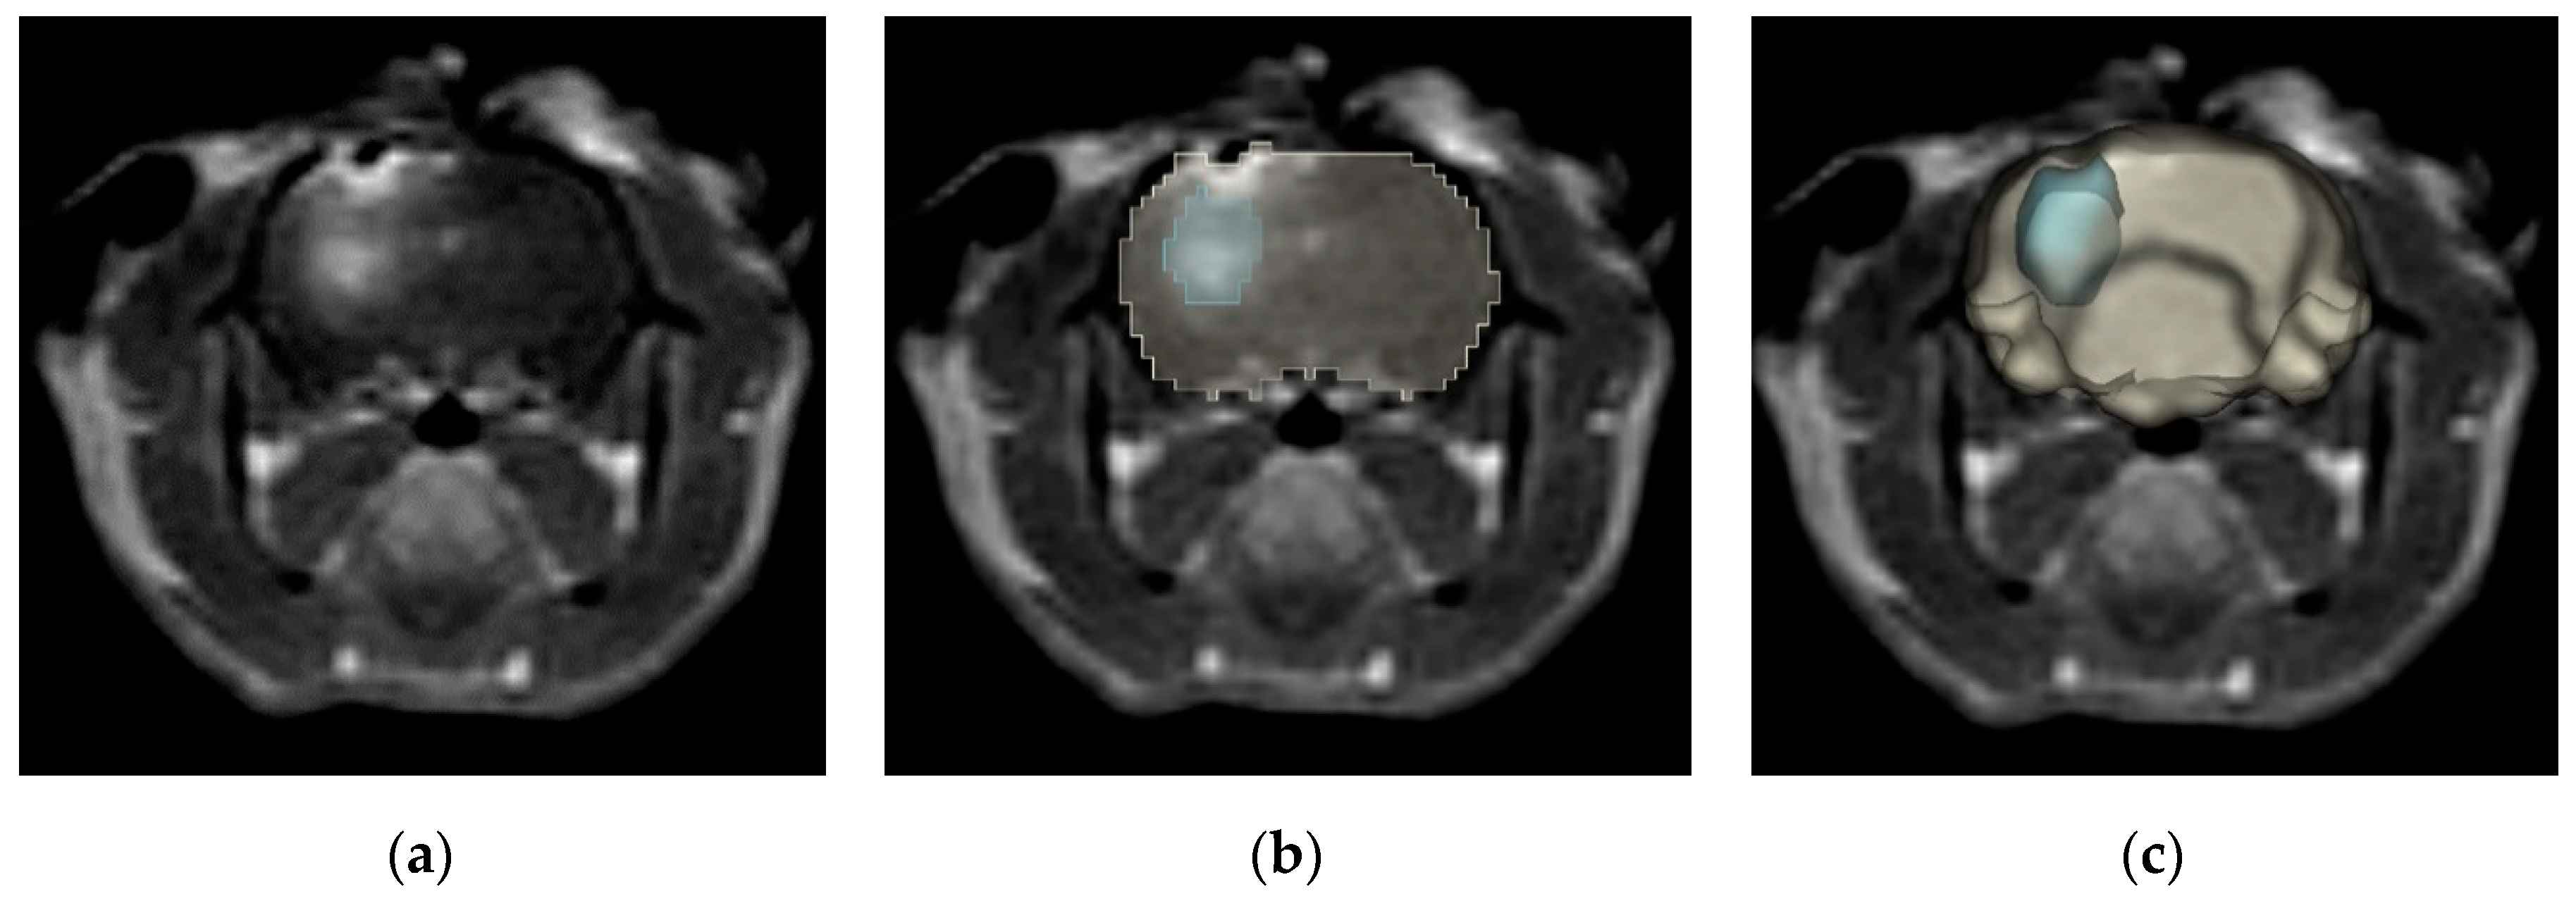

2.1. High-Frequency Electroporation BBBD Analysis

2.1.1. Temporal BBBD Characterization

4.3. Magnetic Resonance Imaging and Gd-EBD BBB Disruption Volumetrics